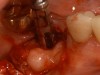

Figure 11 – Internal connection implant system – implant placed post-extraction

Figure 11

Figure 12 – Prefabricated zirconia abutment fitting the internal connection in Figure 11

Figure 12

Figure 13 – Zirconia abutment torque onto implant

Figure 15 – Extraction of anterior tooth No. 8 without detaching the gingiva.

Figure 15

Figure 16 – Extracted tooth with the root canal material (gutta percha) extending from the apex

Figure 16

Figure 17– A zircon (white) abutment was attached immediately after extraction and implant placement.

Figure 17

Figure 18 – Immediate placement of temporary crown over the abutment; laser crown lengthening was performed on the adjacent teeth to improve gingival symmetry

Figure 18

Figure 19 – Four months after surgery with temporary crown over the implant at No. 8.

Figure 19